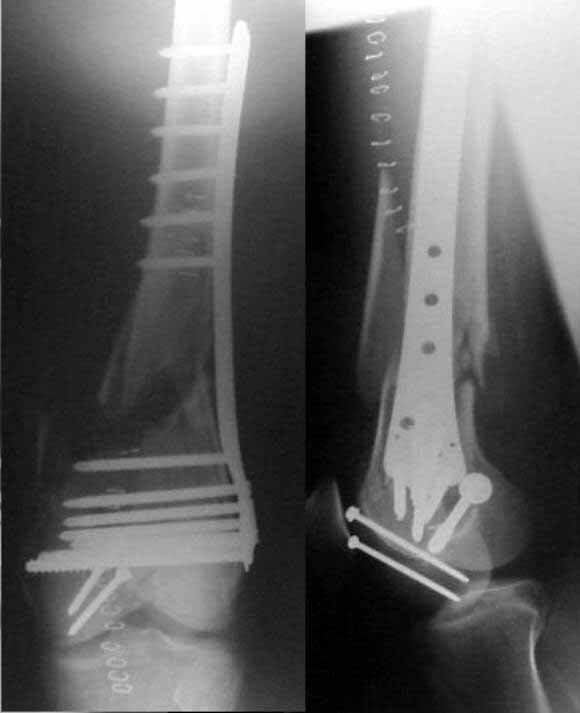

This is the salvage of the failed LISS that I sent to the list on Sept.

Sorry for the delay in posting what we did.

We checked the stability of the intercondylar fracture and it was ok.

But to reassure ourselves we added an intercondylar compression screw, posterior to the LISS.

Then, we performed an standard approach to the thigh and removed all screws in the proximal part of the fracture except two. As seen on the x-ray all screws in the proximal part had been pulled out, but the holes were centered in the middle of the shaft.

Using the two screws left, we repositioned the plate in the same two holes and then drilled bicortical locking screws (green ones) ordered specially for the occasion (they dont come in the same box than the LISS).

We checked the alignment, that was considered good.

These are the post-op x-rays

JMMV> These are the post-op x-rays

Excellent job. But difficult.

In case of such fracture gap probability of nonunion is >0, so dynamization could be useful trick. I wonder whether closed nailing would have been easier to accomplish. It could provide more controllable fixation with less soft tissue stripping. In our settings antegrade nailing works pretty fine in such fractures and it looks like motivation to migrate to LISS is not enough... Any suggestions?